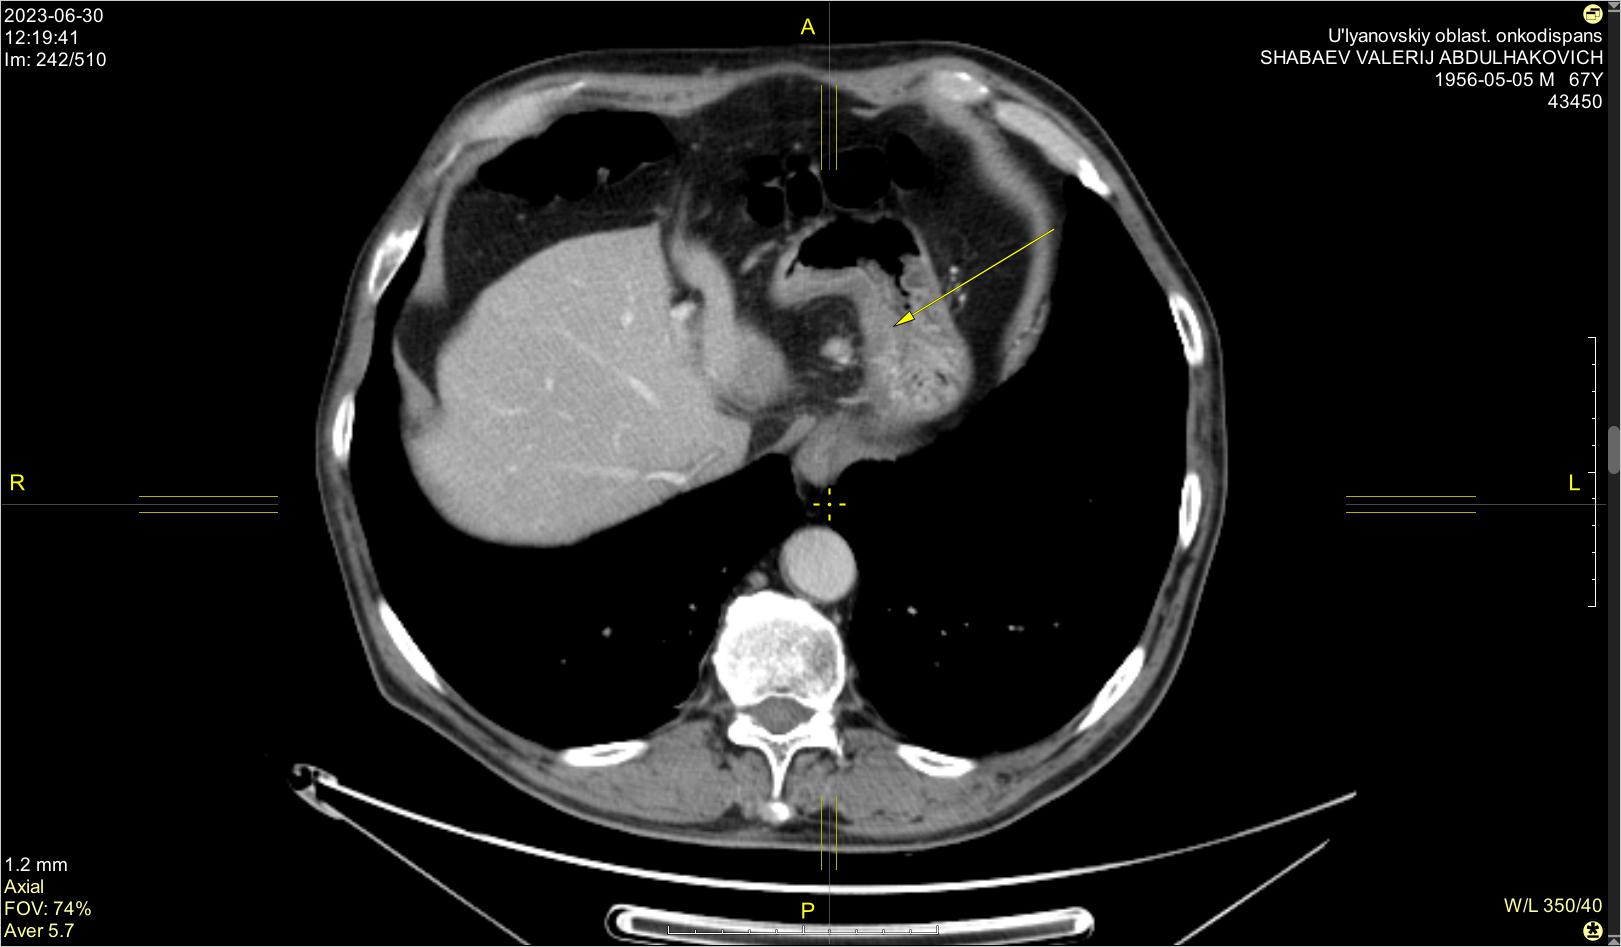

Материал и методы. Представлено 3 клинических случая одновременного развития плоскоклеточного рака пищевода и аденокарциномы желудка у пациентов, получавших лечение в ГУЗ «Областной клинический онкологический диспансер», г. Ульяновск, и ГАУЗ СО «Свердловский областной онкологический диспансер», г. Екатеринбург. Пациентам проведены хирургическое вмешательство, химиотерапия и лучевая терапия.

Результаты. Первично-множественный синхронный плоскоклеточный рак пищевода и аденокарцинома желудка представляют собой сложную клиническую задачу, требующую вмешательства мультидисциплинарной команды специалистов. Химиолучевая терапия с использованием схемы FOLFOX продемонстрировала хорошую переносимость и позволила достичь удовлетворительного клинического ответа со стороны опухолей обеих локализаций.